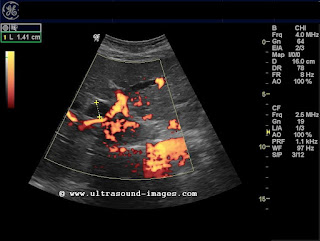

A case of right iliac fossa pain in a child:

This 8 yr old girl had severe right iliac fossa pain and tenderness.

Ultrasound and color Doppler images of the right hemipelvis and right iliac region show a severely swollen appendix (the diameter varied from 8 to 12 mm.) with considerable hyperemia of the wall (see the color Doppler images). The tubular structure showed typical gut signature, one of the hallmarks of Gastro intestinal tract ultrasonography. There is also a large inhomogenous collection with echogenic debris anterior to the appendix, possibly an abscess (peri-appendicular)- (M or ABS)